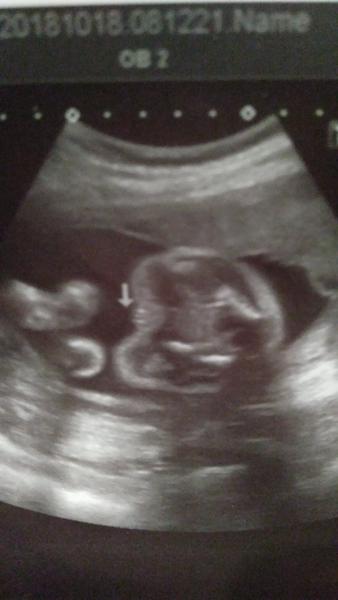

Ahoj holky, tak jsem konečně doma. Klárka je v pořádku, pěkně sebou vrtěla. Je stale v příčné poloze. Dr. zkontroloval vnitrni jizvu po předchozí sekci. Moc se na to netvaril, rikal, že to musíme hlídat. Rekl mi, ze se malá narodí sekcí a ze si mne prevezme v mělnické porodnici (kde pracuje jako externi lékař) do svých rukou. Tak se mi trochu ulevilo, ze vim, ze budu v dobrých rukách. Jinak mi jsme resili termin. Pokud nebudou komplikace, tak by to videl nejlip na 38tt. Jinak prikladam fotecku, kde je hezky zachycené přirození.

@jessulka Skvělé zprávy. Aspoň si můžeš být jistá pohlavím 😉

Klárku moc pozdravujeme 😍

@dominika963852 Děkujeme a Klárka mává z bříška. Vypadala spokojeně.